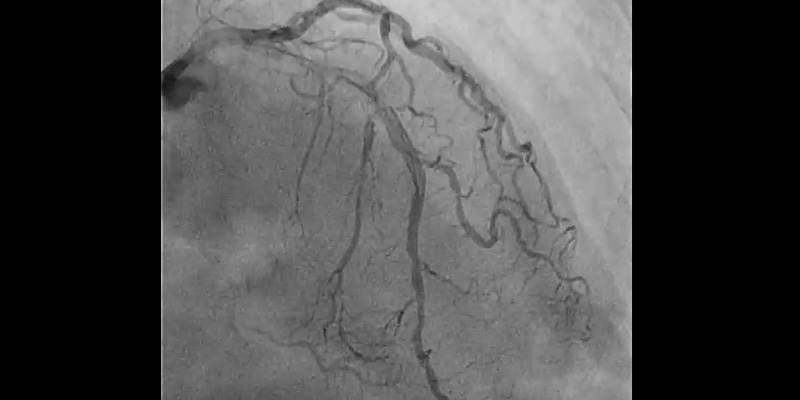

• 2nd Rotational atherectomy with a 1.25mm burr: RotawireTM was placed again through the 6Fr radial catheter and rotablation was performed with a new 1.25 mm burr. Multiple runs were completed until there was no resistance through the lesion or drop in RPM.

• Control angiography showed dissection at bifurcation involving the ostium of the first diagonal branch. With the help of a dual-lumen catheter, a second wire was placed into the diagonal branch.

• IVUS (OptiCrossTM IVUS catheter) showed plaque rupture after rotablation at different levels. However, a calcium ring of more than 270º was observed at the site of maximum plaque.

• For this reason, plaque modification was completed with a 2.5x6mm FlextomeTM Cutting BalloonTM.

• Finally, provisional stenting of mid LAD (2.75x24 mm Synergy stent) and post-dilatation with a NC EmergeTM (3.0x12 mm) showed a good result when confirmed with IVUS. Dissection on the diagonal was still present, with a TIMI 3 flow.